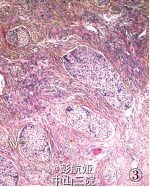

患者,62 岁,因发现右乳肿物 1 年,腹痛、腹胀 20 天伴血便入院。 查体:乳腺右侧外上象限触及一直径约 4 cm 肿物,质硬,活动,与周围界较清;左侧盆腔包块,直径约 11 cm。影像学检查:钼靶显示右乳腺浅分叶状高密度影,边界尚清,无钙化及毛刺征;CT 平扫盆腔类圆形实性肿块影,边界清晰,瘤体内见不定形钙化,结肠部分肠腔狭窄,肠壁增厚;遂行结肠镜检查示乙状结肠可见肿物,覆脓苔,质脆。 血清中 CEA 70. 23μg/ ml、CA125 422.15 KU/ L,CA199 137.53 U/ml。 遂行右乳肿物切除术 + 乙状结肠癌切除术及左侧附件切除术。 术中所见:右乳肿物分叶状,与周围界清;乙状结肠肿物与周围无粘连;左侧卵巢肿物包膜完整,未见腹水。 术后病理显示右乳腺内分泌癌,乙状结肠腺癌,左侧卵巢 Brenner 瘤。病理检查摇 眼观:右乳肿物 1 个,大小 3.5 cm *3 cm *2cm,无明确包膜,分叶状,切面灰白,质脆;结肠见一溃疡性肿物,大小 3. 5 cm *3 cm *1. 5 cm,切面灰白色,质脆,侵及全层;左侧卵巢肿物 1 个,大小 8 cm *6.5 cm*5 cm,包膜完整,切面淡黄色,质韧。 镜检:乳腺肿瘤由密集排列的细胞巢 组成,被纤细的纤维血管间质分隔,部分细胞呈短梭形,部分呈浆细胞样,可见菊形团结构(图 1);(结肠)肠壁间及浆膜下脂肪组织可见大部分癌组织排列成腺腔样,小部分呈片状分布,细胞核深染,异型明显,间质纤维化明显(图 2);卵巢肿瘤纤维瘤样间质中见巢状、岛状的移行细胞,瘤细胞呈咖 啡豆样,有纵行核沟,胞质丰富,嗜酸性,部分细胞巢中央有空腔(图 3)。 免疫表型:乳腺肿瘤 CgA(图 4)、NSE、CK、ER和 PR 均( + ),60% 细胞 Syn(图 5)( + ),HerbB-2、CA125 均( - );卵巢肿瘤 CK7、CK5/6 均( + ),Ki-67( - )。病理诊断:右乳神经内分泌癌;结肠腺癌;左侧卵巢Brenner 瘤。